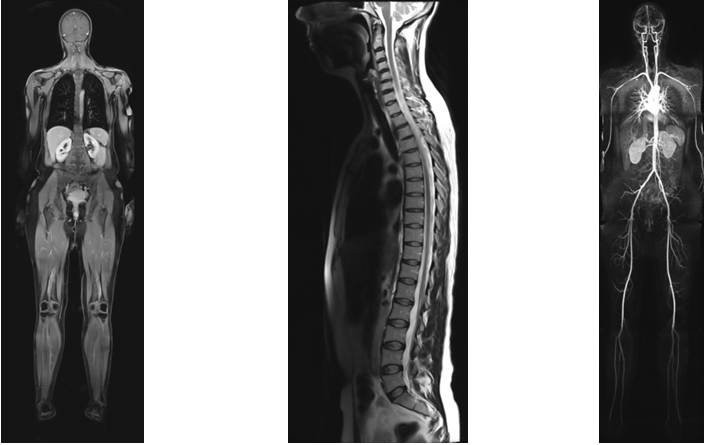

2. Tumorvorsorge und Veränderungen im Körper: MRT-Ganzkörperuntersuchung

- Untersuchung beinhaltet:

- Kopf mit Halsgefäßen

- Hals- und Thoraxbereich

- Abdomen-Beckenorgane: Leber, Gallenblase, Milz, Bauchspeicheldrüse, Nieren, Nebennieren und Harnblase

- bei Frauen: Gebärmutter, Eierstöcke und Eileiter

- bei Männern: Samenblasen und Prostata auf Wunsch mit PSA-Wert

- Lymphknotenstatus

- Wirbelsäule: orientierende Messung über der LWS; optional HWS oder BWS

- Gelenke und Weichteile: orientierende Messungen der Schulter-, Hüft-, Knie- und Sprunggelenke

- technisch bedingt können das Herz, die Brust und der Dickdarm in dieser Untersuchung nicht beurteilt werden